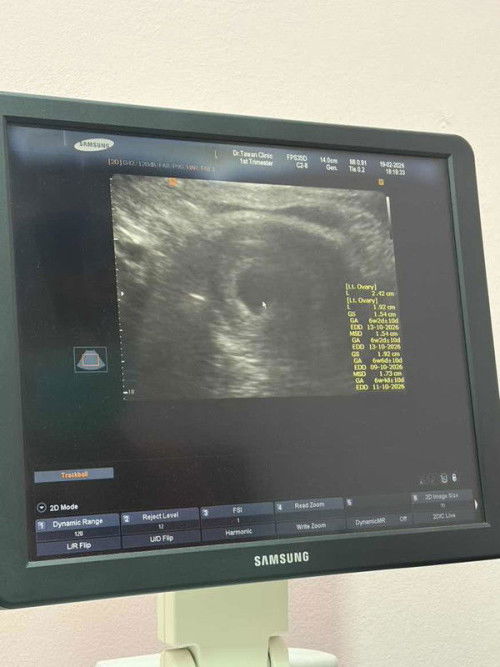

ตัวอ่อนไปฝังตัวตรงท่อนำไข่ คิดว่าหมอจะเอาเด็กออกไหมค่ะแล้วเอาออกวิธีไหน ตอนนี้มีรังไข่แค่ข้างเดียวกลัวเขาตัดรังไข่ทิ้งมาก ท้อง7 สัปดาห์ค่ะ เครียดไปหมดเลยค่ะ ไม่มีอาการปวดท้องเลยเลือดท้องเล็กน้อย กลัวมีลูกไม่ได้อีกรอบที่สองของการท้องนอกมดลูก ทำให้มีรังไข่เหลือข้างหนึ่ง หมอยังไม่บอกว่าจะจัดการยังไง #ขอคำแนะคำปรึกษาคะ #ทางนี้กังวลมากค่ะ #ขอบคณสำหรับคำตอบล่วงหน้านะคะ